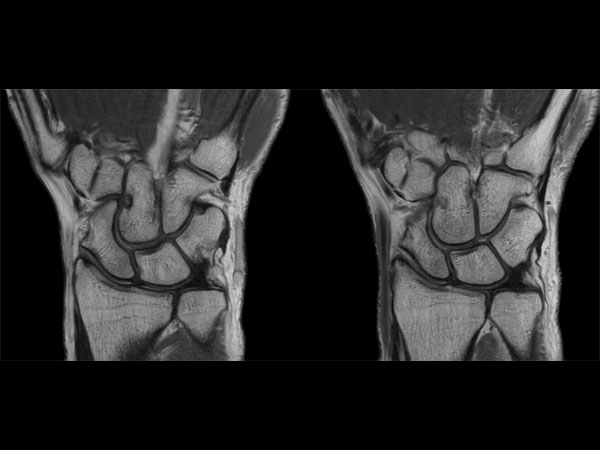

Wrist Imaging

Comprehensive Wrist imaging